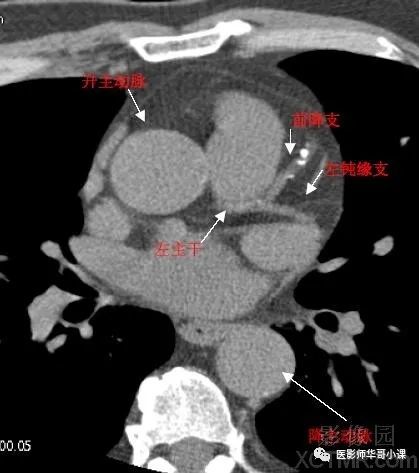

【高清ct图】心脏冠脉cta解剖

cta冠脉解剖必点收藏